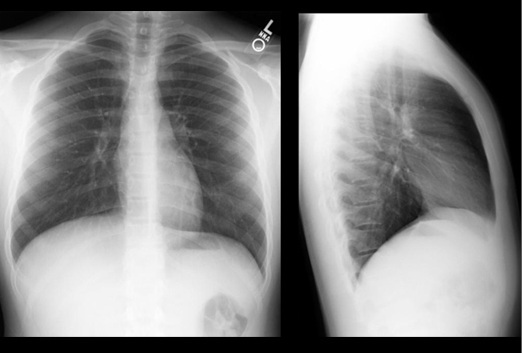

Sebuah rontgen pada dada, mengambil gambar dari jantung, paru, pembuluh darah, saluran pernafasan, dan kelenjar getah bening di daerah ini. Tulang dada, tulang rusuk, dan tulang selangka juga masuk dalam gambar. Gambar ini juga menunjukkan bagian atas tulang belakang. Rontgen dada digunakan untuk mendiagnosis masalah kesehatan yang menimbulkan gejala di daerah dada seperti masalah paru dan pernafasan serta gangguan jantung. Pada kebanyakan kasus, rontgen dada melibatkan dua gambar, yaitu gambar yang diambil dari belakang, dan satu lagi diambil dari samping.